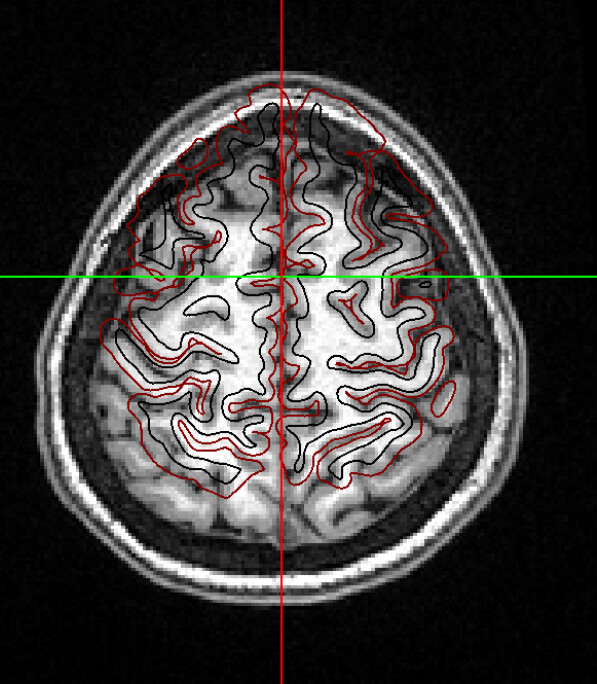

I’m using xcp_d for post-process the output from fmriprep. I found misalignment between t1w and atlas almost all the subjects, similar to the case here but with worse result:

And I’m not sure if this is the reason of why there exist some ROIs with N/A timeseries signal in the mean_timeseries.tsv

I checked the report of fmriprep and I think the results of spatial normalization as well as alignment are correct.